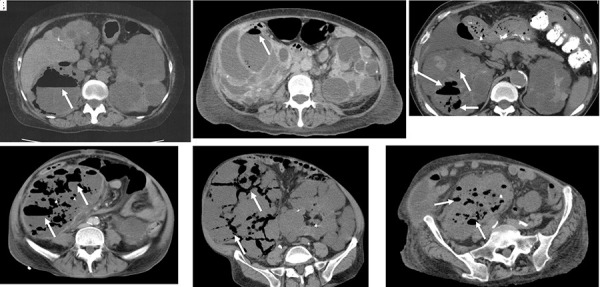

肺气肿性多囊肾感染(EPRI)预后差,需要保守治疗,建议早期手术切除肾。然而,经皮囊肿引流可能是一种可能的治疗选择。我们研究了6例常染色体显性多囊肾病(ADPKD),并伴有EPRI。3例患者在肾经动脉栓塞(TAE)后发生EPRI, 3例患者独立于肾经动脉栓塞发生EPRI。2例患者仅有1个囊肿伴气体形成,病原菌对抗生素敏感;经囊肿引流及抗生素治疗均治愈。但3例严重肾肿大、多发囊肿造气患者,因病原菌对抗生素耐药,囊肿引流无效,行手术切除肾,得到有效治疗。多发囊肿伴气体形成及严重肾肿大的患者应考虑手术切除肾。

Emphysematous polycystic renal infection (EPRI) has a poor prognosis with conservative management, and early surgical nephrectomy has been recommended. However, percutaneous cyst drainage may be a possible treatment option. We experienced 6 patients with autosomal dominant polycystic kidney disease (ADPKD) presenting with EPRI. Three patients developed EPRI after renal transarterial embolization (TAE), and the other 3 developed EPRI independently of renal TAE. Two of the patients had only one cyst with gas formation, and the causative organism was sensitive to antibiotics; these patients were cured by cyst drainage and antibiotic therapy. However, in 3 patients with severe renal enlargement and gas formation in multiple cysts, the causative organism was antibiotic resistant and cyst drainage was not effective, so surgical nephrectomy was performed and the disease effectively treated. Surgical nephrectomy should be considered in patients with multiple cysts with gas formation and severe renal enlargement.